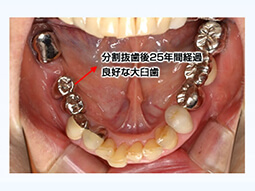

長期経過症例は語る(“何もしない”コンセプトの可能性について)

貴重な症例から学ぶ事はないか…歯科医師目線で探ってみましょう。

上下20本の歯で30年間何でも噛めてます!(残存歯22本、この45年間に失った歯は僅か1本!)

81歳女性 昭和43年より当院に通院、初診より45年経過

ここで注目すべき点は28本全ての歯が無くとも噛めている事です。勿論噛めなければ人工的な咀嚼回復治療は必要ですが、“噛める”“噛めない”の判断は患者様が判断することです。ただ歯の数が少ない事だけを理由に直ちに義歯、インプラント治療が必要であるとは限りません。患者様が日常生活上全く支障が無ければ“何もしない”ことも一つの選択肢であることをこの症例は語っています。

オランダを中心とした1部のヨーロッパ諸国ではこの“何もしない” コンセプト(shortened Dental Arch Concept)は浸透してるようですが学術的には顎関節への影響、上顎前突、反対咬合、などの不正咬合は研究対象から除外されている事など一人ひとりの患者様に注意深い対応が求められます。